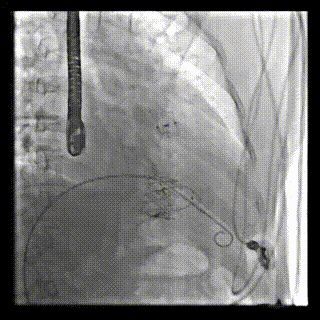

本周三例接受LuX-Valve Plus經(jīng)血管三尖瓣置換術(shù)的患者中,第一例患者為冠狀動(dòng)脈旁路移植術(shù)+Bentall+二尖瓣成形術(shù)后;第二例患者為永久起搏器植入術(shù)后,存在跨三尖瓣導(dǎo)線;第三例患者合并房顫、房缺及左心耳封堵術(shù)后。

三例患者入院后,葛均波院士團(tuán)隊(duì)周達(dá)新教授、潘文志教授、張?jiān)床┦?、陳莎莎博士及心超室的潘翠珍教授、李偉教?/strong>對(duì)患者的情況進(jìn)行詳細(xì)評(píng)估和討論,最終決定為三例患者選擇LuX-Valve Plus40mm、50mm和50mm型號(hào)的瓣膜進(jìn)行手術(shù)治療。手術(shù)后即刻拔除氣管插管,術(shù)后患者三尖瓣反流癥狀得到顯著改善,復(fù)查心超結(jié)果顯示人工三尖瓣瓣膜支架固定穩(wěn)定,瓣葉關(guān)閉形態(tài)未見(jiàn)異常,未見(jiàn)明顯反流。

LuX-Valve Plus是LuX-Valve系列產(chǎn)品的第二代,采用的是經(jīng)血管入路的全新輸送系統(tǒng),其設(shè)計(jì)開發(fā)過(guò)程得到了上海中山醫(yī)院葛均波院士及其團(tuán)隊(duì)的精心指導(dǎo),研究結(jié)果提示瓣膜植入的安全性和有效性俱佳,尤其瓣膜獨(dú)特的設(shè)計(jì)使其具有極佳自適應(yīng)性,本周三例患者病因及解剖結(jié)構(gòu)各具特點(diǎn),但均可從LuX-Valve Plus植入術(shù)明顯獲益。目前,LuX-Valve Plus已在全國(guó)各中心開展救治性臨床研究,相信未來(lái)定會(huì)為更多的三尖瓣反流患者帶來(lái)福音。